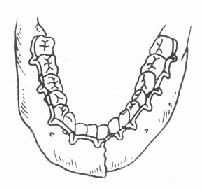

1.单颌牙弓夹板固定法:是用直径2毫米的铝丝或成品带钩牙弓夹板,按牙弓形态成形,然后用较细的金属结扎丝穿过牙间隙,将牙弓夹板结扎在骨折线两侧的部分或全部牙齿上(图4-18),以固定骨折段。这种方法适用于无明显移位的骨折,如下颌骨颏部正中线性骨折、局限性牙槽突骨折。

单颌牙弓夹板固定

图4-18 单颌牙弓夹板固定图4-19 颌间牵引固定法